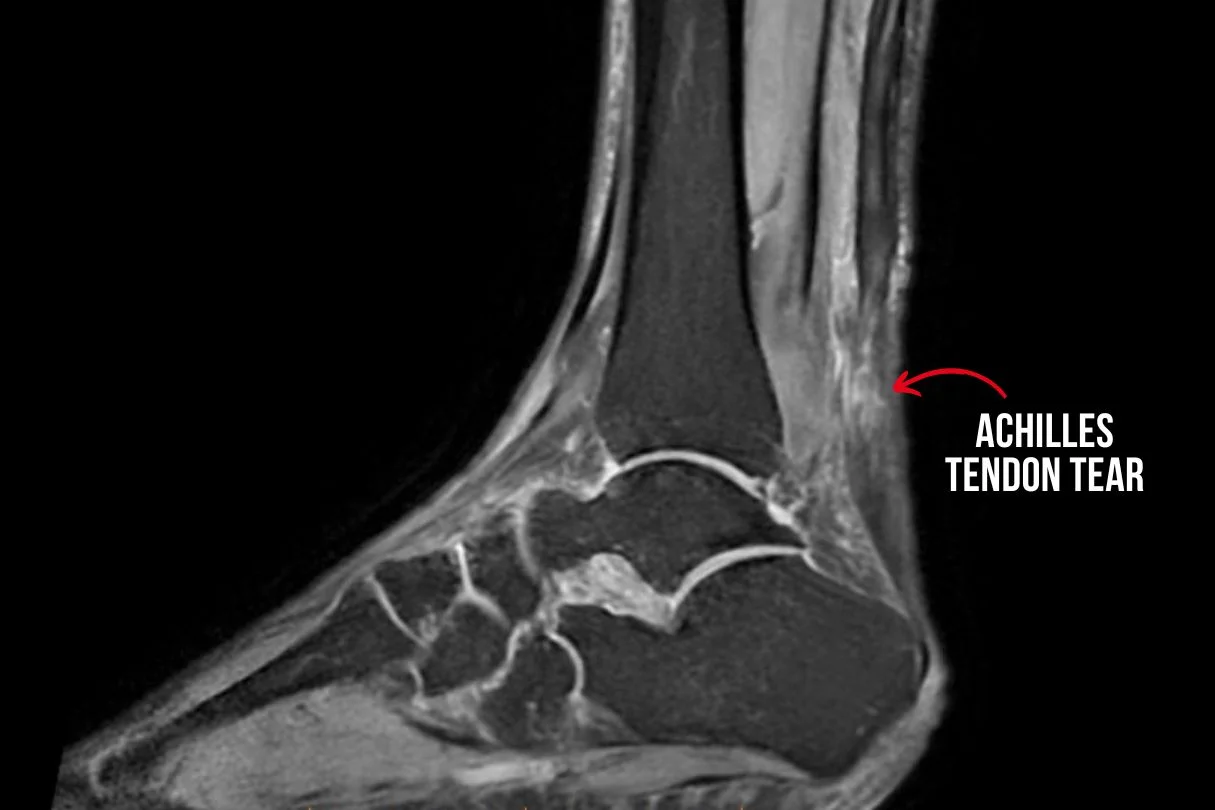

Diagnostic tests such as ultrasound or MRI scans are typically necessary to confirm the extent of the injury. Treatment options will depend on the severity of the tear but commonly include: